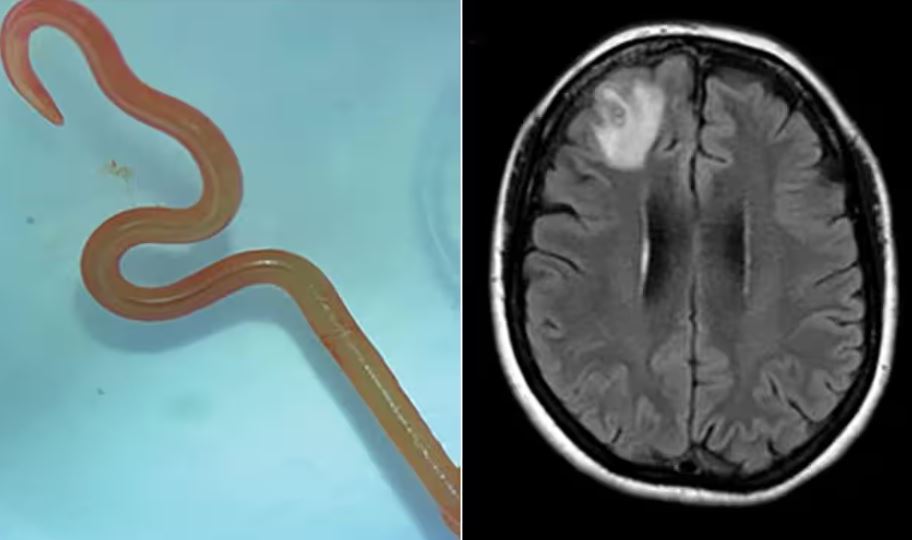

وقام الأطباء بسحب دودة حية  طولها 8 سم توجد عادة في الثعابين من دماغ امرأة تبلغ من العمر 64 عامًا من جنوب شرق نيو ساوث ويلز باستراليا.

وبحلول عام 2022، شملت أعراضها أيضًا النسيان والاكتئاب، مما دفعها إلى إحالتها إلى مستشفى كانبيرا حيث كشف فحص التصوير بالرنين المغناطيسي لدماغها عن وجود تشوهات تتطلب عملية جراحية.

وتابع: "كانبيرا مكان صغير، لذلك أرسلنا الدودة، التي كانت لا تزال على قيد الحياة، مباشرة إلى مختبر أحد العلماء  الذي يتمتع بخبرة كبيرة في مجال الطفيليات"، لقد نظر إليها وقال: هذه دودة مستديرة توجد عادة في الثعابين، وهي أول حالة في العالم للطفيل الذي يتم العثور عليه في البشر.